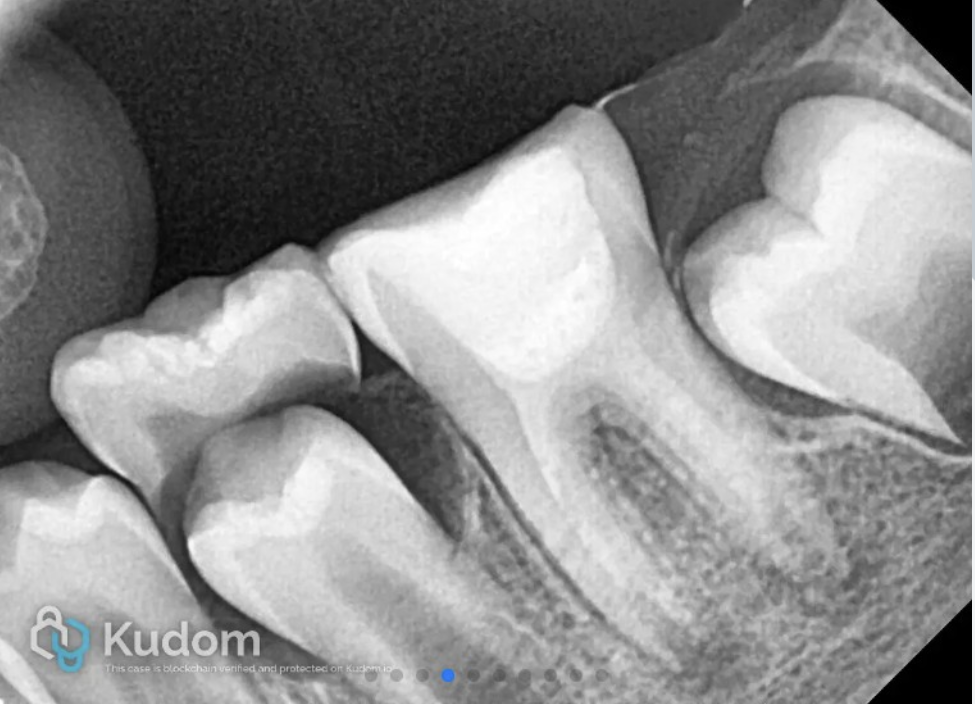

An 8-year-old female patient reported to the clinic with complaint of pain in left mandibular molar tooth. Clinical and radiographic examinations revealed a carious nonvital 36 with immature root apex. The stage of root maturity corresponded with Demirjian’s stage G (wide open apical foramen and nearly completed root length).

The X-ray shows deep carious lesion in tooth 36. The root length is nearly complete with wide open apical foramina and indistinct apical lamina dura around both mesial and distal roots.